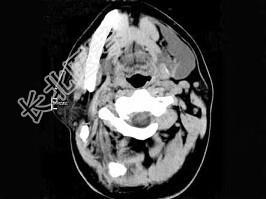

- 单项选择题男,32岁, 左侧下颌部肿块,CT如图所示, 最可能的诊断是 ( )

A、造釉细胞瘤

B、颌骨囊肿

C、鳃裂囊肿

D、颈部淋巴管瘤

E、舌下腺囊肿